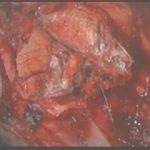

術中写真

摘出 前